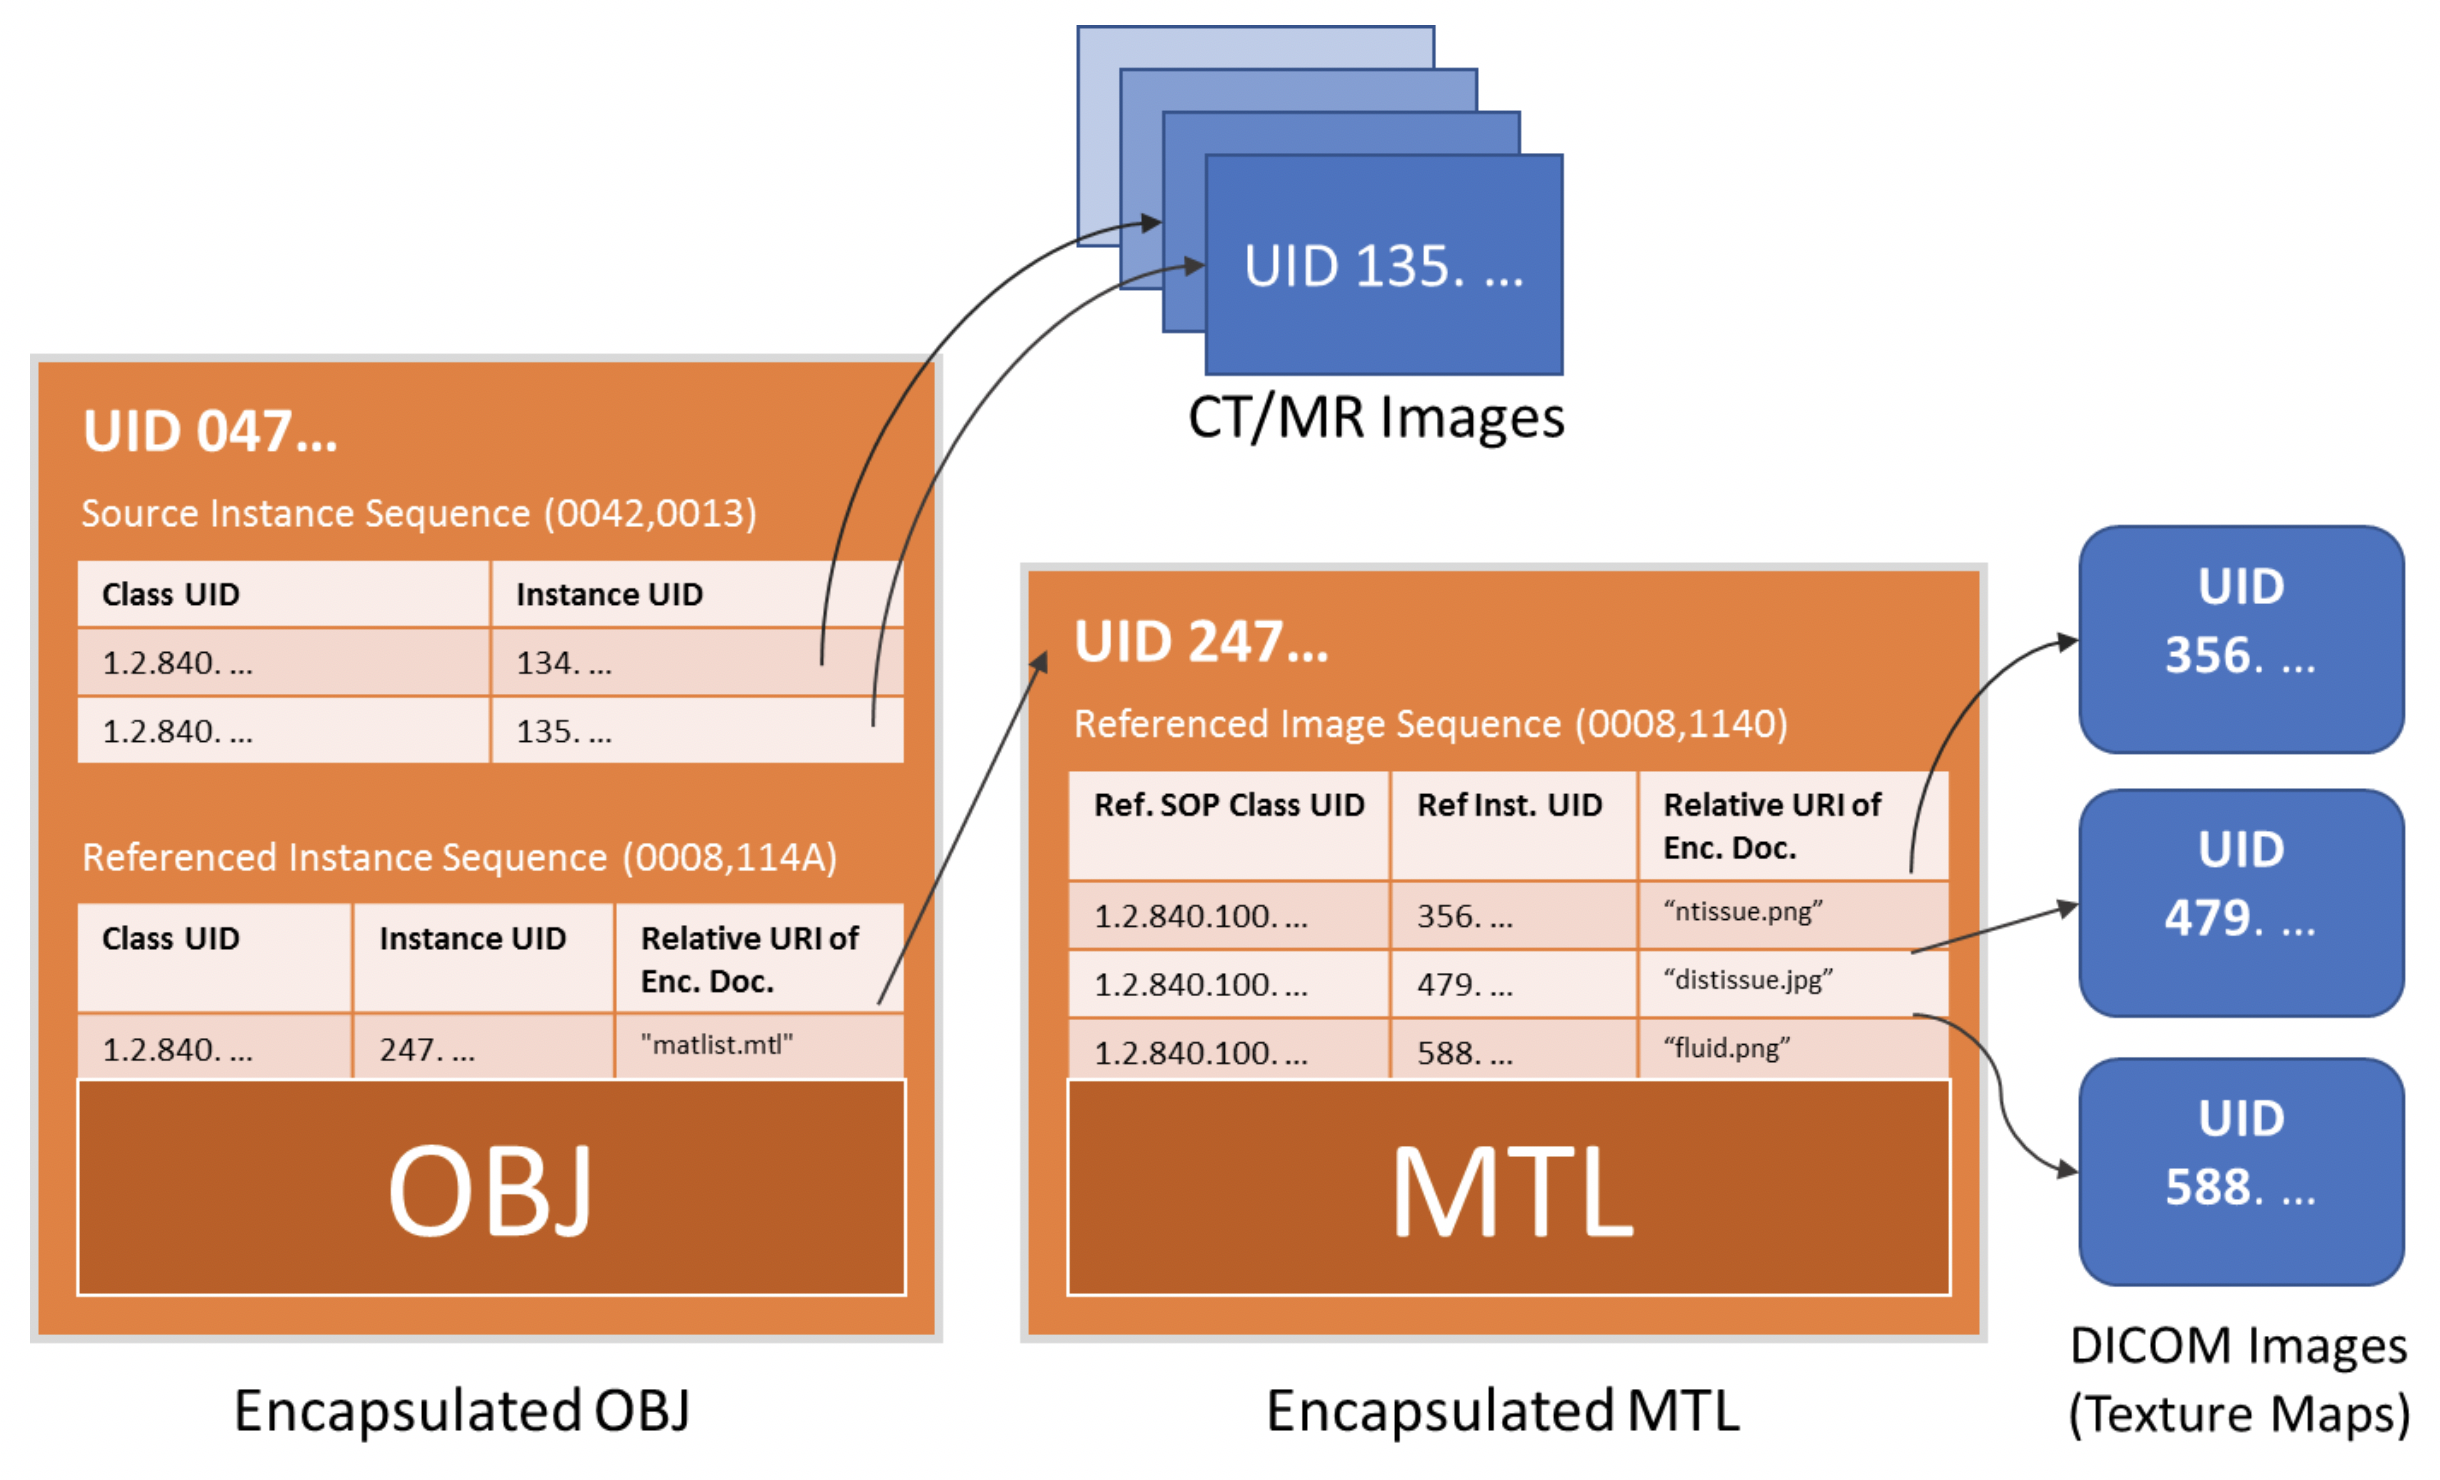

- RRRR.1-1. Relationship between OBJ, MTL and Texture Map image files and corresponding DICOM Instances